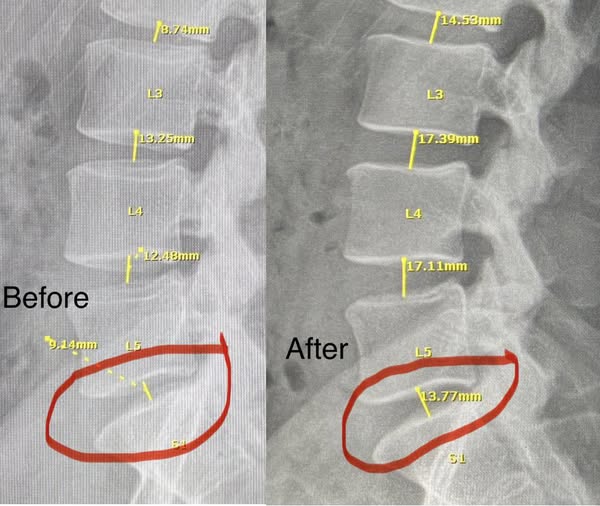

Spinal Evaluation & Imaging Review

Our team will review any existing X-rays or imaging to assess disc health

Reducing pressure inside bulging and herniated discs

Creating a gentle negative pressure that may help retract disc material

Improving the circulation of oxygen and nutrients to the injured area

Allowing discs to rehydrate and heal